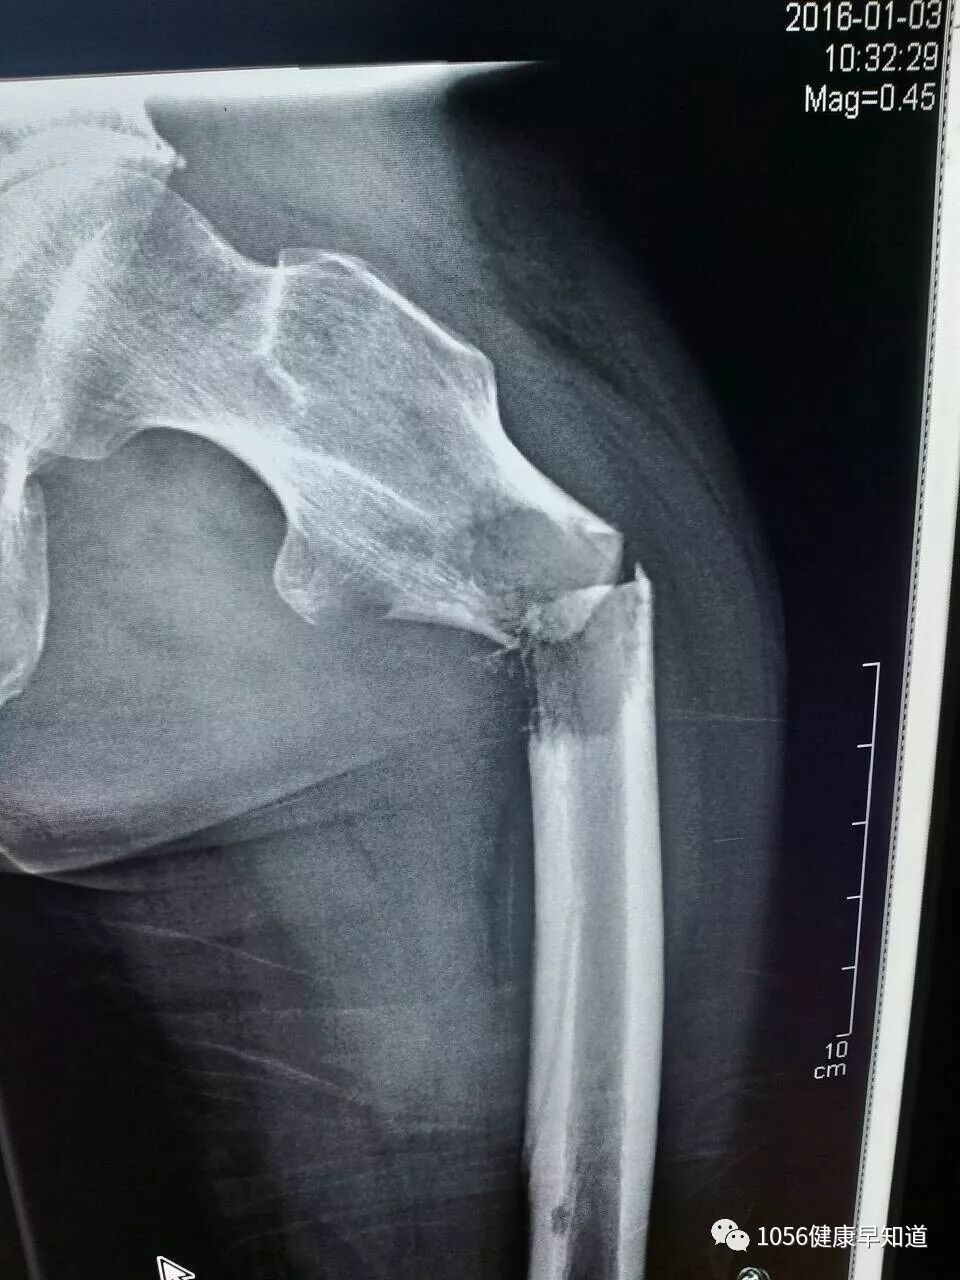

骨转移瘤是指恶性肿瘤细胞通过血道播散等方式转移到骨骼,并在骨骼局部生长,造成骨破坏。骨转移瘤多发生在脊椎、骨盆、肋骨等部位,会引起骨痛、病理性骨折(轻微外力即造成骨折),脊椎转移还可发生脊髓压迫以至截瘫。骨转移常见于鼻咽癌、乳腺癌、前列腺癌、甲状腺癌、肺癌、肾癌等。

一提肿瘤骨转移,大家的第一反应就是疼痛。事实上,骨转移瘤并非一开始就会出现骨痛,很多肿瘤患者,全身骨扫描或局部骨骼磁共振出现骨破坏,但没有骨痛。临床上,有些病人是因为骨痛才发现骨转移,有些人则是没有骨痛,而是因为轻微外伤后的病理性骨折就诊才发现骨转移。但不论肿瘤患者发生骨转移是否伴有骨痛,都需要及时开始积极治疗。

当确诊发生骨转移瘤后,应及时积极综合治疗。综合来讲就是在抗原发肿瘤治疗基础上进行姑息治疗,以提高整体的生活质量。一方面是积极治疗原发肿瘤,阻止患者体内产生更多的肿瘤细胞,使身体状况变的更差;另一方面,使用双膦酸盐类药物,减少骨骼破坏,降低骨折、疼痛等症状对患者造成的损害,提高生活质量;第三方面,注意避免病理性骨折的发生。事实上,骨转移瘤一般不直接威胁生命,当肿瘤细胞转移到骨骼后,它们在骨骼局部生长,主要的危害是造成骨破坏。骨转移除了引起疼痛外,还可能出现功能障碍、病理性骨折、高钙血症等一系列骨骼并发症,脊椎转移还可发生脊髓压迫以至截瘫,这些临床上称为“骨相关事件”。只要发现了骨转移瘤,即使还没有症状,也应该开始治疗。目的就是避免疼痛、骨折甚至瘫痪等“骨相关事件”的发生。积极预防骨折和瘫痪尤其重要,因为一旦骨转移患者发生瘫痪,生活质量就大打折扣,甚至坠积性肺炎、褥疮等并发症威胁生命的程度较原发肿瘤更严重。